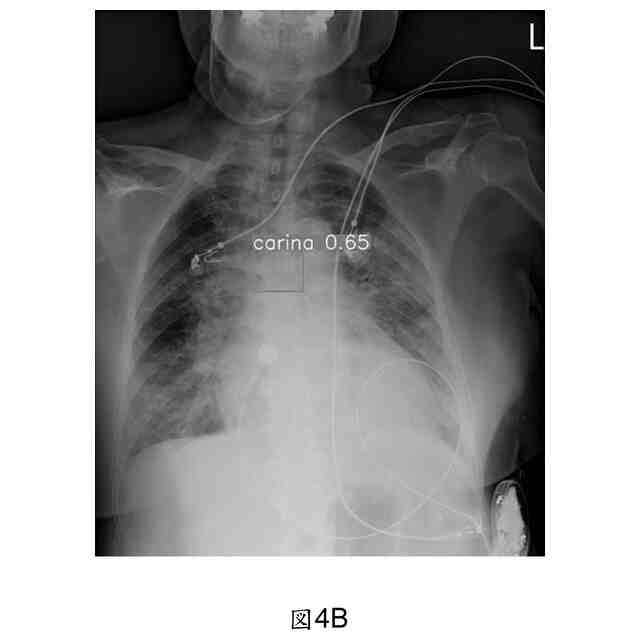

当該位置評価モジュールは、気管内チューブ先端と気管カリーナとの距離を測定し、識別した気管内チューブ先端の注釈境界ボックスの下端から、左端と右端の座標点を選び出して、関数で、2点間の中間点を計算し、それが、ユークリッド距離公式で当該3点と気管カリーナの距離値を利用して、計算した最も短い距離を選び出し、また、当該距離に対して、画像のピクセル値を、対応する実際の距離値に変換する、ことを特徴とする、請求項1に記載される気管内チューブの位置異常な警告装置。

当該位置評価モジュールは、気管内チューブの先端位置が、気管カリーナより低い時、或いは、気管内チューブ先端と気管カリーナとの距離が、3cmより小さい時や5cmより大きい時、アラームをトリガーする、ことを特徴とする、請求項1に記載される気管内チューブの位置異常な警告装置。

本発明は、上記らの目的を達成するため、気管内チューブの設置位置の正確性を監視する、気管内チューブの位置異常な警告装置であって、患者の胸部X線の画像素材を収集する、監視モジュールと、当該監視モジュールに接続されて、当該監視モジュールから入力された当該胸部X線の画像素材を受信し、人工知能(Artificial Intelligence, AI)計算モデルで、画像上の気管カリーナ(tracheal carina)や、気管内チューブ(endotracheal tube, ETT)及び気管切開チューブ(tracheostomy tubes)の存在を識別して、その位置を注釈する、物件検知モジュールと、当該物件検知モジュールに接続され、当該物件検知モジュールが、気管カリーナや気管内チューブの存在を検知した時、当該人工知能計算モデルの判断結果の注釈位置に基づいて、自動的に、気管内チューブの先端と気管カリーナとの距離を測定し、また、求めた距離の数値に基づいて、気管内チューブの位置適当性に対して、評価結果を生成し、当該評価結果において、当該気管内チューブの位置が、正確範囲内に位置しない時、アラームをトリガーする、位置評価モジュール及び、当該位置評価モジュールに接続され、当該物件検知モジュールと当該位置評価モジュールの判断結果を受信して、警告信号を発して、また、物件の注釈結果や気管内チューブの位置適当性の当該評価結果を表示する、表示モジュールと、が含まれる。